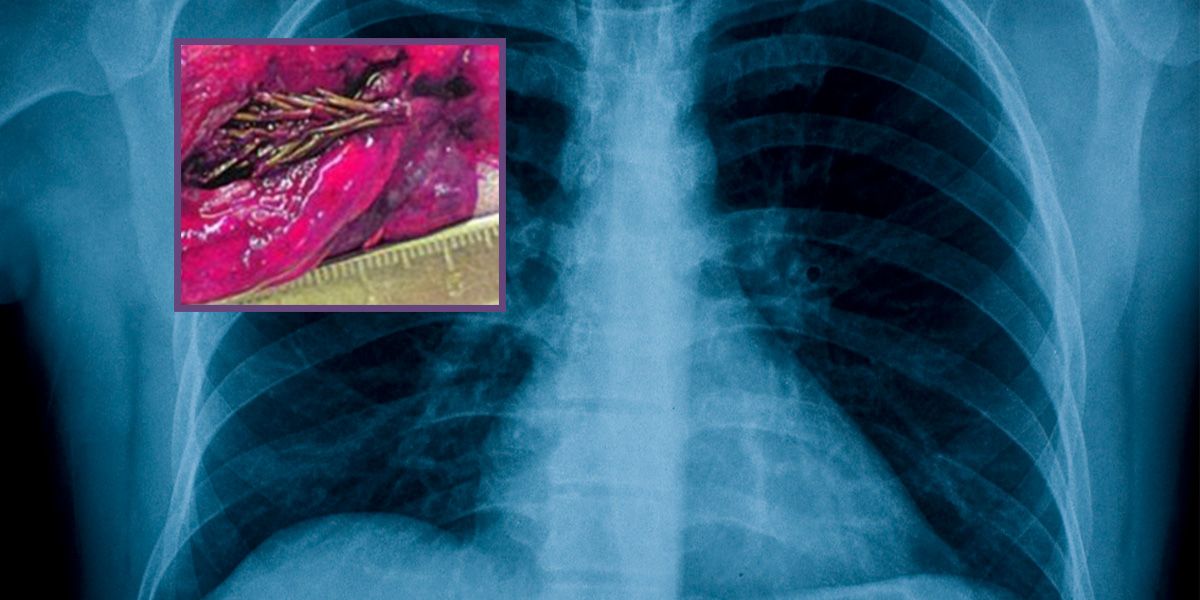

Diesen kleinen Tannenzweig (kl. Bild) fanden die Ärzte in der Lunge des Patienten.